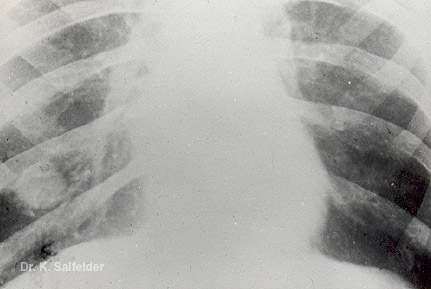

Abb. 11,3: Kokzidioidomykose

Tumorfoermiger Knoten in einem Lungenuntelappen (mykot. Pseudotumor)